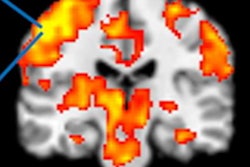

Before exercise, fMRI showed significantly greater activation in the right angular gyrus brain region for patients with Gulf War illness compared with the other two groups. After exercise, patients with Gulf War illness had significantly less activation in the cerebellar vermis and right intraparietal sulcus than their counterparts.

Conversely, fMRI revealed significantly greater activation in the left rolandic operculum among chronic fatigue syndrome subjects compared with the other two groups and greater activation than Gulf War illness cases in both the periaqueductal gray and right insula. The researchers found no significant changes in brain region activation before or after exercise among the healthy control subjects.

"In short, peri-insular neural activity differentiates chronic fatigue syndrome from Gulf War illness and controls, whereas medial cerebellar activity differentiates Gulf War illness from chronic fatigue syndrome and controls," they noted. "These findings suggest qualitatively different neural substrates of postexertional malaise associated with cognition in Gulf War illness and chronic fatigue syndrome."

The insula region of the brain (right column) has greater activation in individuals with chronic fatigue syndrome than in healthy controls or those with Gulf War illness. By comparison, the cerebellum (middle column) has less activation in Gulf War illness than healthy controls or those with chronic fatigue syndrome. In addition, the brainstem showed less activation (left column) in Gulf War illness and greater activation in chronic fatigue syndrome. All the differences were observed after exercise. Images courtesy of Stuart Washington, PhD.In the second study, the researchers compared brain region activation based on blood oxygenation level dependent (BOLD) contrast among 79 veterans with Gulf War illness, 36 people with chronic fatigue syndrome, and 31 healthy controls. The goal was to explore nine brainstem regions of interest and four media structures, all of which are linked to memory performance, to illustrate the degree to which these conditions have differing effects.